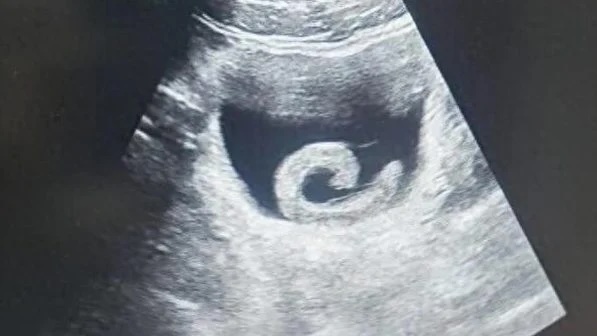

Đỉa dài 10 cm sống ký sinh trong mũi người bệnh. Ảnh: BVCC.